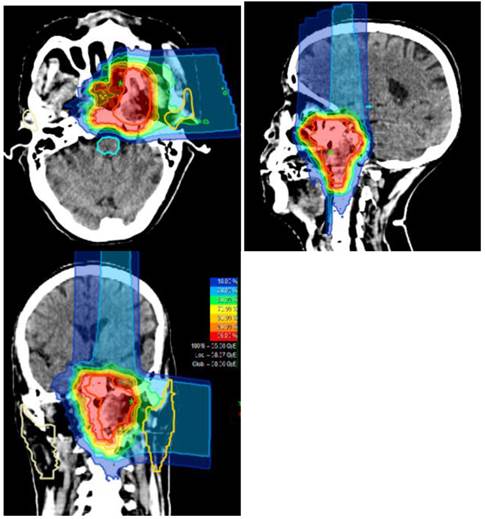

Figure 1

Typical treatment plan and dose distribution for carbon ion radiotherapy delivered using the raster-scanning technique in a patients with locally recurrent nasopharyngeal carcinoma.

CIRT in the form of intensity modulated carbon-ion radiation therapy (IMCT) will be delivered using raster-scanning technology. Patients are treated for once a day, 5 days per week. Treatment interruptions of more than 3 days are not allowed unless severe adverse effects require so. Treatment during weekends are required if a break of 2 or more days occurred during the working days. Patient positioning prior to CIRT will be evaluated by comparison of orthogonal x-rays to the DRRs. Set up deviations >2 mm are corrected prior to treatment delivery. A typical treatment plan is illustrated in Figure 1.